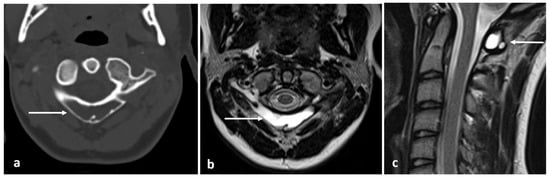

| Osteochondroma | Lesion continuity with cortex and medulla. | Cartilage cap |

| Chondroblastoma | Osteolytic lesion. Variable intralesional calcification (chondroid matrix) | Extraosseous soft tissue component |